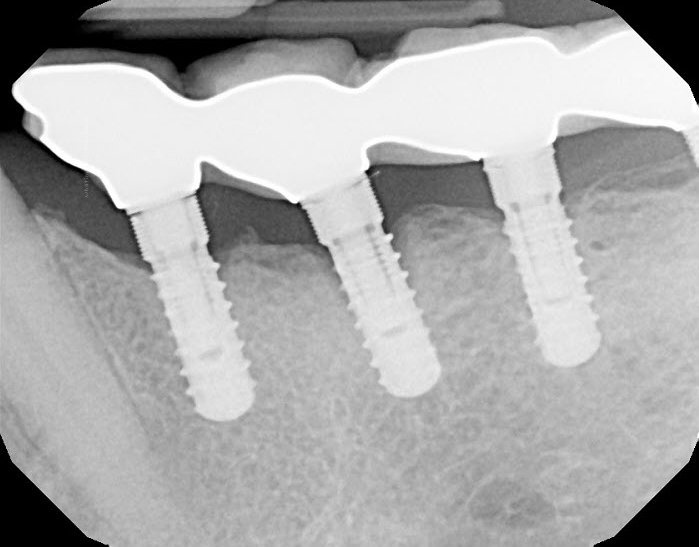

Connection Interface

Internal interface

Body Shape

Non-tapered body

Thread Design

MicrothreadsThreadedRounded threads

Straight flangeCurved apex